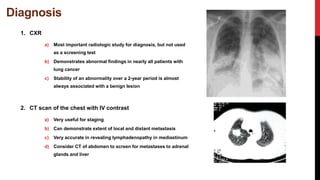

1. CXR

a) Most important radiologic study for diagnosis, but not used

as a screening test

b) Demonstrates abnormal findings in nearly all patients with

lung cancer

c) Stability of an abnormality over a 2-year period is almost

always associated with a benign lesion

2. CT scan of the chest with IV contrast

a) Very useful for staging

b) Can demonstrate extent of local and distant metastasis

c) Very accurate in revealing lymphadenopathy in mediastinum

d) Consider CT of abdomen to screen for metastases to adrenal

glands and liver